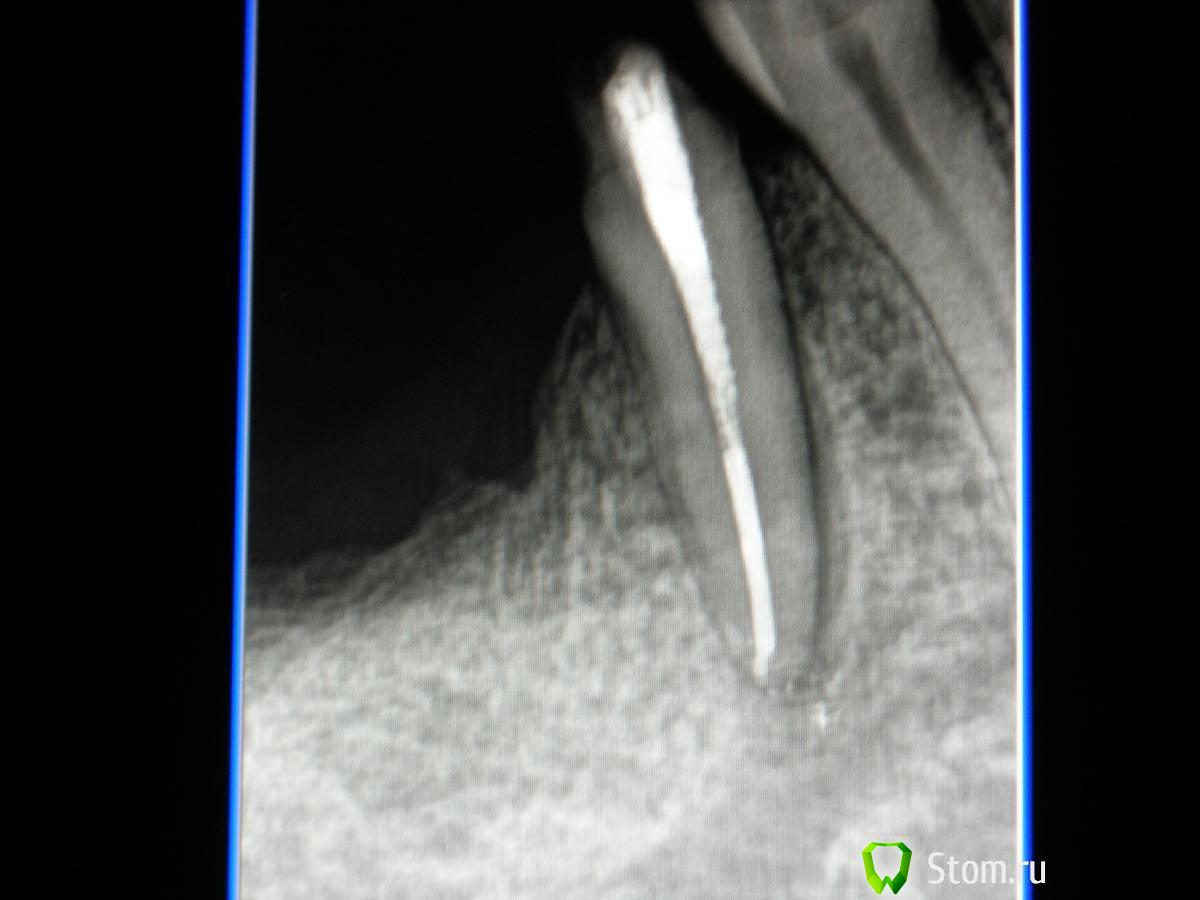

sabi Опубликовано 13 марта, 2012 Поделиться Опубликовано 13 марта, 2012 Дорогие,доктора !Помогите понять в чем причина болей.Начну с начала.В августе 2011 лечила 45 по поводу пульпита.вот контрольный снимок далее этот зуб стал одной из опор мостовидного протеза.Все хорошо,но в декабре появились боли сначала под протезом,а потом и в зубе.Появился свищ,в области межзубного сосочка между 45и46.Вот снимок-в свищ введен гуттаперчевый штифт В итоге мостик сняли,под ним ни пролежней,все чисто.Сейчас зуб беспокоит при накусывании,свищ не уходит,что это может быть?Ортопед настаивает,что я пропустила второй канал.Помогите советом.вот последний снимок Ссылка на комментарий

ger_berra Опубликовано 13 марта, 2012 Поделиться Опубликовано 13 марта, 2012 На пропущеный канал не похоже.На предмет наличия трещины надо проверить,согласна.Этот мост представляет собой рычаг,который постепенно вывихивает 45 зуб.Обратите внимание на периодонтальную щель дистально.Она расширена от коронки до апекса.Своеобразное ортодонтическое перемещение 45 в сторону 46 и одновременно функциональная перегрузка.Если уж и ставить в данном случае мост,то под опору нужно было взять и 44.Либо на место 46 имплант.Я так вижу. Ссылка на комментарий

Каплан Опубликовано 13 марта, 2012 Поделиться Опубликовано 13 марта, 2012 (изменено) ну судя по наклону моляра, это все же 8, а не 7. слишком много места для одного моляра при таком наклоне дистальной опоры.+1 за трещину - условия есть (анкер). Прощупайте борозду по кругу шаг за шагом, каждый миллиметр... должен быть одиночный резкий карман. особенно медиально... слишком в этом месте расширение щели... Если трещины нет, возможно просто функциональная перегрузка... Изменено 13 марта, 2012 пользователем Каплан Ссылка на комментарий

О4ень добрbIй д@нтист Опубликовано 13 марта, 2012 Поделиться Опубликовано 13 марта, 2012 Когда будете вынимать титановый штифт, трещина себя покажет в полной красе. Ссылка на комментарий